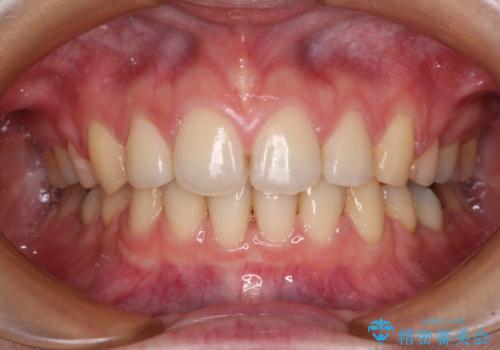

上顎前突とディープバイト ワイヤー矯正での確実に仕上げる

- 深く咬みこみ、前に飛び出した上顎前歯を気にして来院された患者様です。

口元の突出感はあまりありませんでしたが、上顎歯列が全体的に前方にあり、更には下顎歯列が深く咬みこんでいるために、上顎前歯が前方に突出している状態でした。

抜歯は行わず、補助装置を用いて上顎歯列全体を後方移動させ、ワイヤー装置にて奥歯の咬み合わせを改善していくこととしました。

正面や横から見た印象が同じで用であっても、奥歯の咬み合わせが理想的であるかどうかによって、治療の難易度は大きく異なります。

こちらの方も難易度のやや高い状態で、2年以上の期間が予想されましたが、想定通りの2年強で治療を終えることができました。